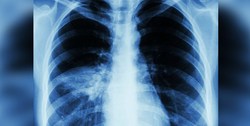

به گزارش آوای نشاط، در بیشکک، برخی رسانههای منطقهای از افزایش قابل توجه افراد مبتلا به ذات الریه در ترکمنستان خبر میدهند.

بر اساس اطلاعات پزشکان مرکز جلوگیری و درمان از بیماریهای عفونی، برخی بیماران در شرایط بحرانی مراجعه میکنند و حتی موارد درگذشت بیماران ثبت شده است.

به گفته پزشکان احتمالا این افراد مبتلا به ویروس کرونا بوده اما دولت اجازه انجام تست تشخیصی نمیدهد.

شایان ذکر است که تاکنون دولت ترکمنستان از ثبت موارد کرونا در این کشور خبری منتشر نکرده است.